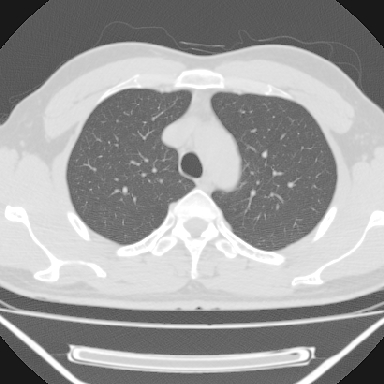

标题: CT6237:右上后纵隔旁肿块影

m 30 右胸痛10年

病灶与椎间孔间存在脂间隙,病灶较大,椎间无明显异常改变,与胸膜移行处可见尾状影,考虑胸膜肿瘤,以良性间皮瘤可能性大

病灶最大径线处于肋间隙,不排除起源于肋神经源性肿瘤

右上后纵隔旁软组织肿块影,与肺界面光滑,与胸壁呈钝角相交,提示肺外病变。位于肋骨下缘,边缘清楚,呈三角样指向与右侧椎间孔,但并示进入椎间孔;与对侧神经根对比,属同一走行方向。

考虑后纵膈良性肿瘤,神经源性肿瘤可能大。

鉴别:胸膜来源肿瘤。影像表现虽有肺外征象,但无胸水等相应佐证;再者,病史前10年,超长,与胸膜肿瘤不太吻合。

建议:再次查体,问清疼痛部位,如为1~2个肋间痛则神经源性肿瘤可能大,如疼痛较弥散,不按肋间分布,则可能为后纵膈其它来源肿瘤。

良性胸膜间皮瘤可能性大,神经源性肿瘤可能性小,因为没有见到有瘤体组织伸入神经孔内!

右上后纵隔脊柱旁见长椭圆形肿块,边界光整,与胸壁呈钝角。周围骨质未见异常。

考虑、1、后纵隔神经源性肿瘤;

2、不除外单发胸膜间皮瘤。